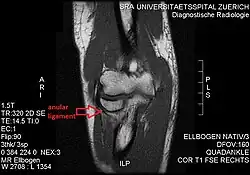

- T1 weighted MRI showing the anular ligament